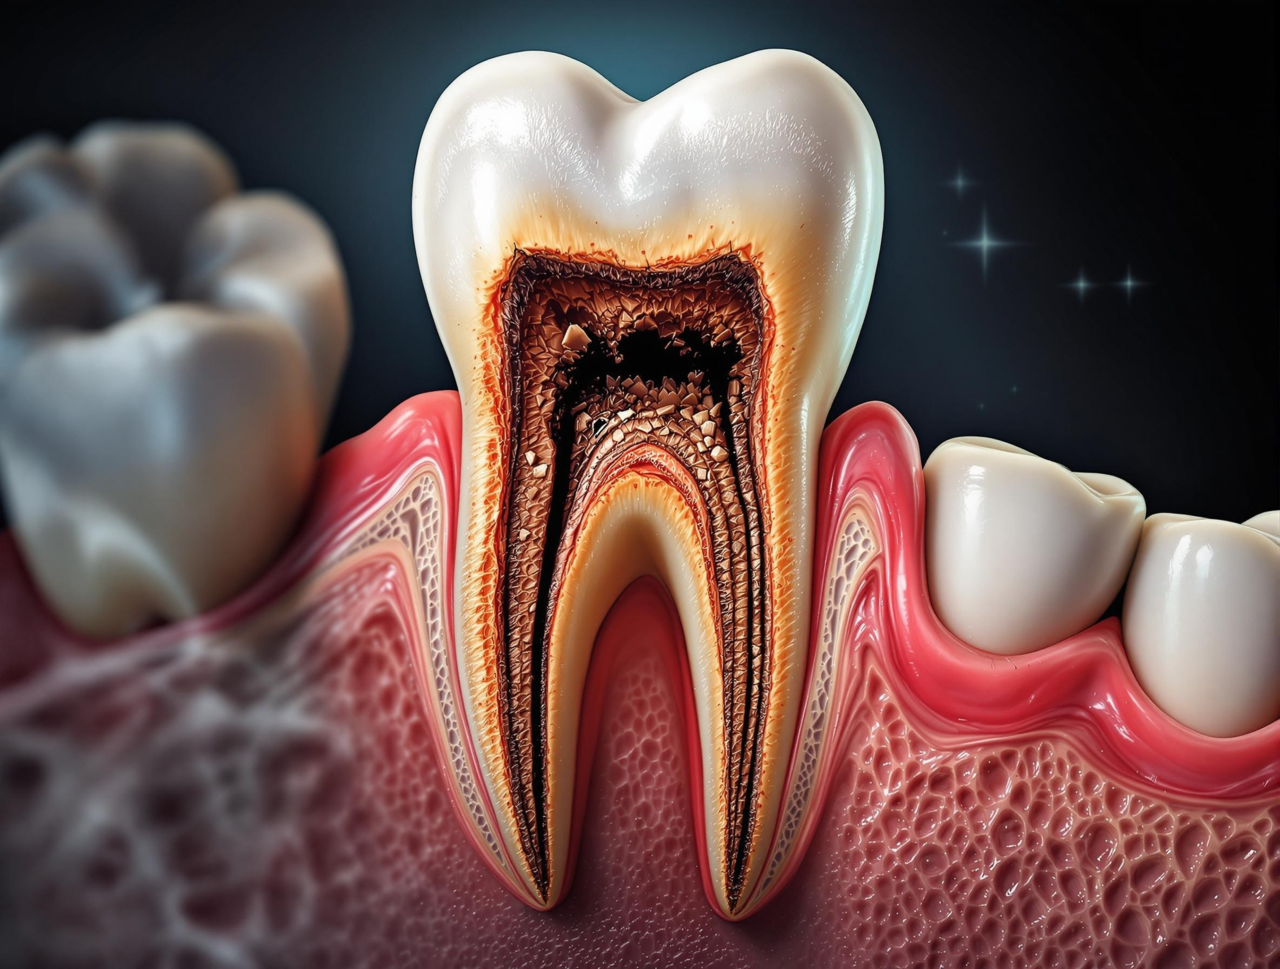

칫솔이 닿지 않는 부위로 인해 사랑니가 부패된다.

사랑니와 인접한 어금니 사이에 음식물이 자주 낀다. 잔여 음식물이 사랑니 주변 치아까지 부패시키는 원인이 된다.